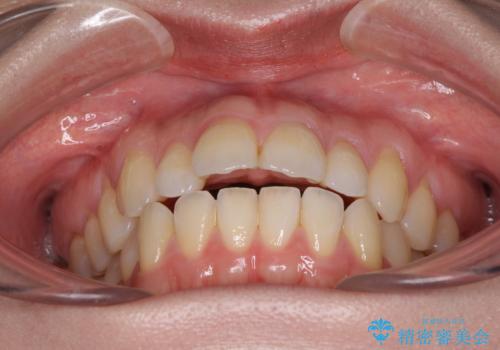

骨格的に下顎がやや前方にあるため、横顔のシルエットが著しく変化することはありませんでしたが、口元はスッキリと引っ込み、唇が閉じやすくなりました。